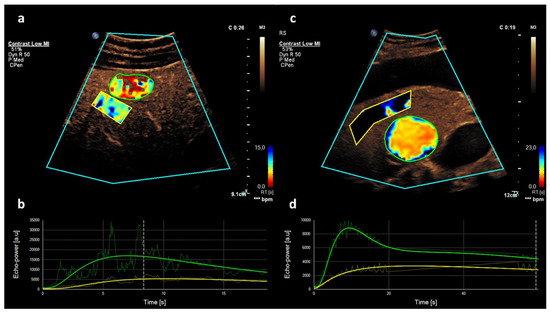

2.2. CEUS

2.3. Quantitative CEUS Assessment